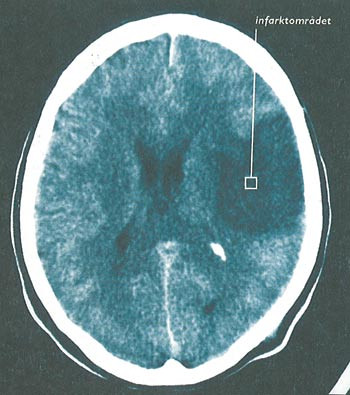

Det oppstår 13 000 – 14 000 hjerneslag (infarkter og blødninger) i Norge hvert år (3). Insidensen er avtakende (4), men økt overlevelse fører til uendret eller økende prevalens (5). Akutte hjerneslag har en mortalitet på ca. 20 % etter 30 dager (6), deretter ytterligere 10 % mortalitet i løpet av ett år. Etter det er det ca. 10 % mortalitet hvert år (7). Nær 20 % overlever med stort funksjonstap, 30 % med moderat funksjonstap og 50 % med liten eller ingen reduksjon av funksjon (8). Postapoplektisk epilepsi utgjør en viktig del av komplikasjonsfrekvensen hos pasienter som overlever et hjerneslag (fig 1).

Patofysiologien bak postapoplektisk epilepsi er lite kartlagt (14). Den iskemiske penumbraen (randsonen) rundt infarktet er trolig substratet for akutte anfall (14). Økt frigjøring av eksitotoksisk glutamat, ioneubalanse, nedbrytning av membranfosfolipider og frigjøring av frie fettsyrer karakteriserer penumbraen (14). Sene (ekte) anfall kan skyldes gliose og utvikling av meningocerebralt cicatrix (20).